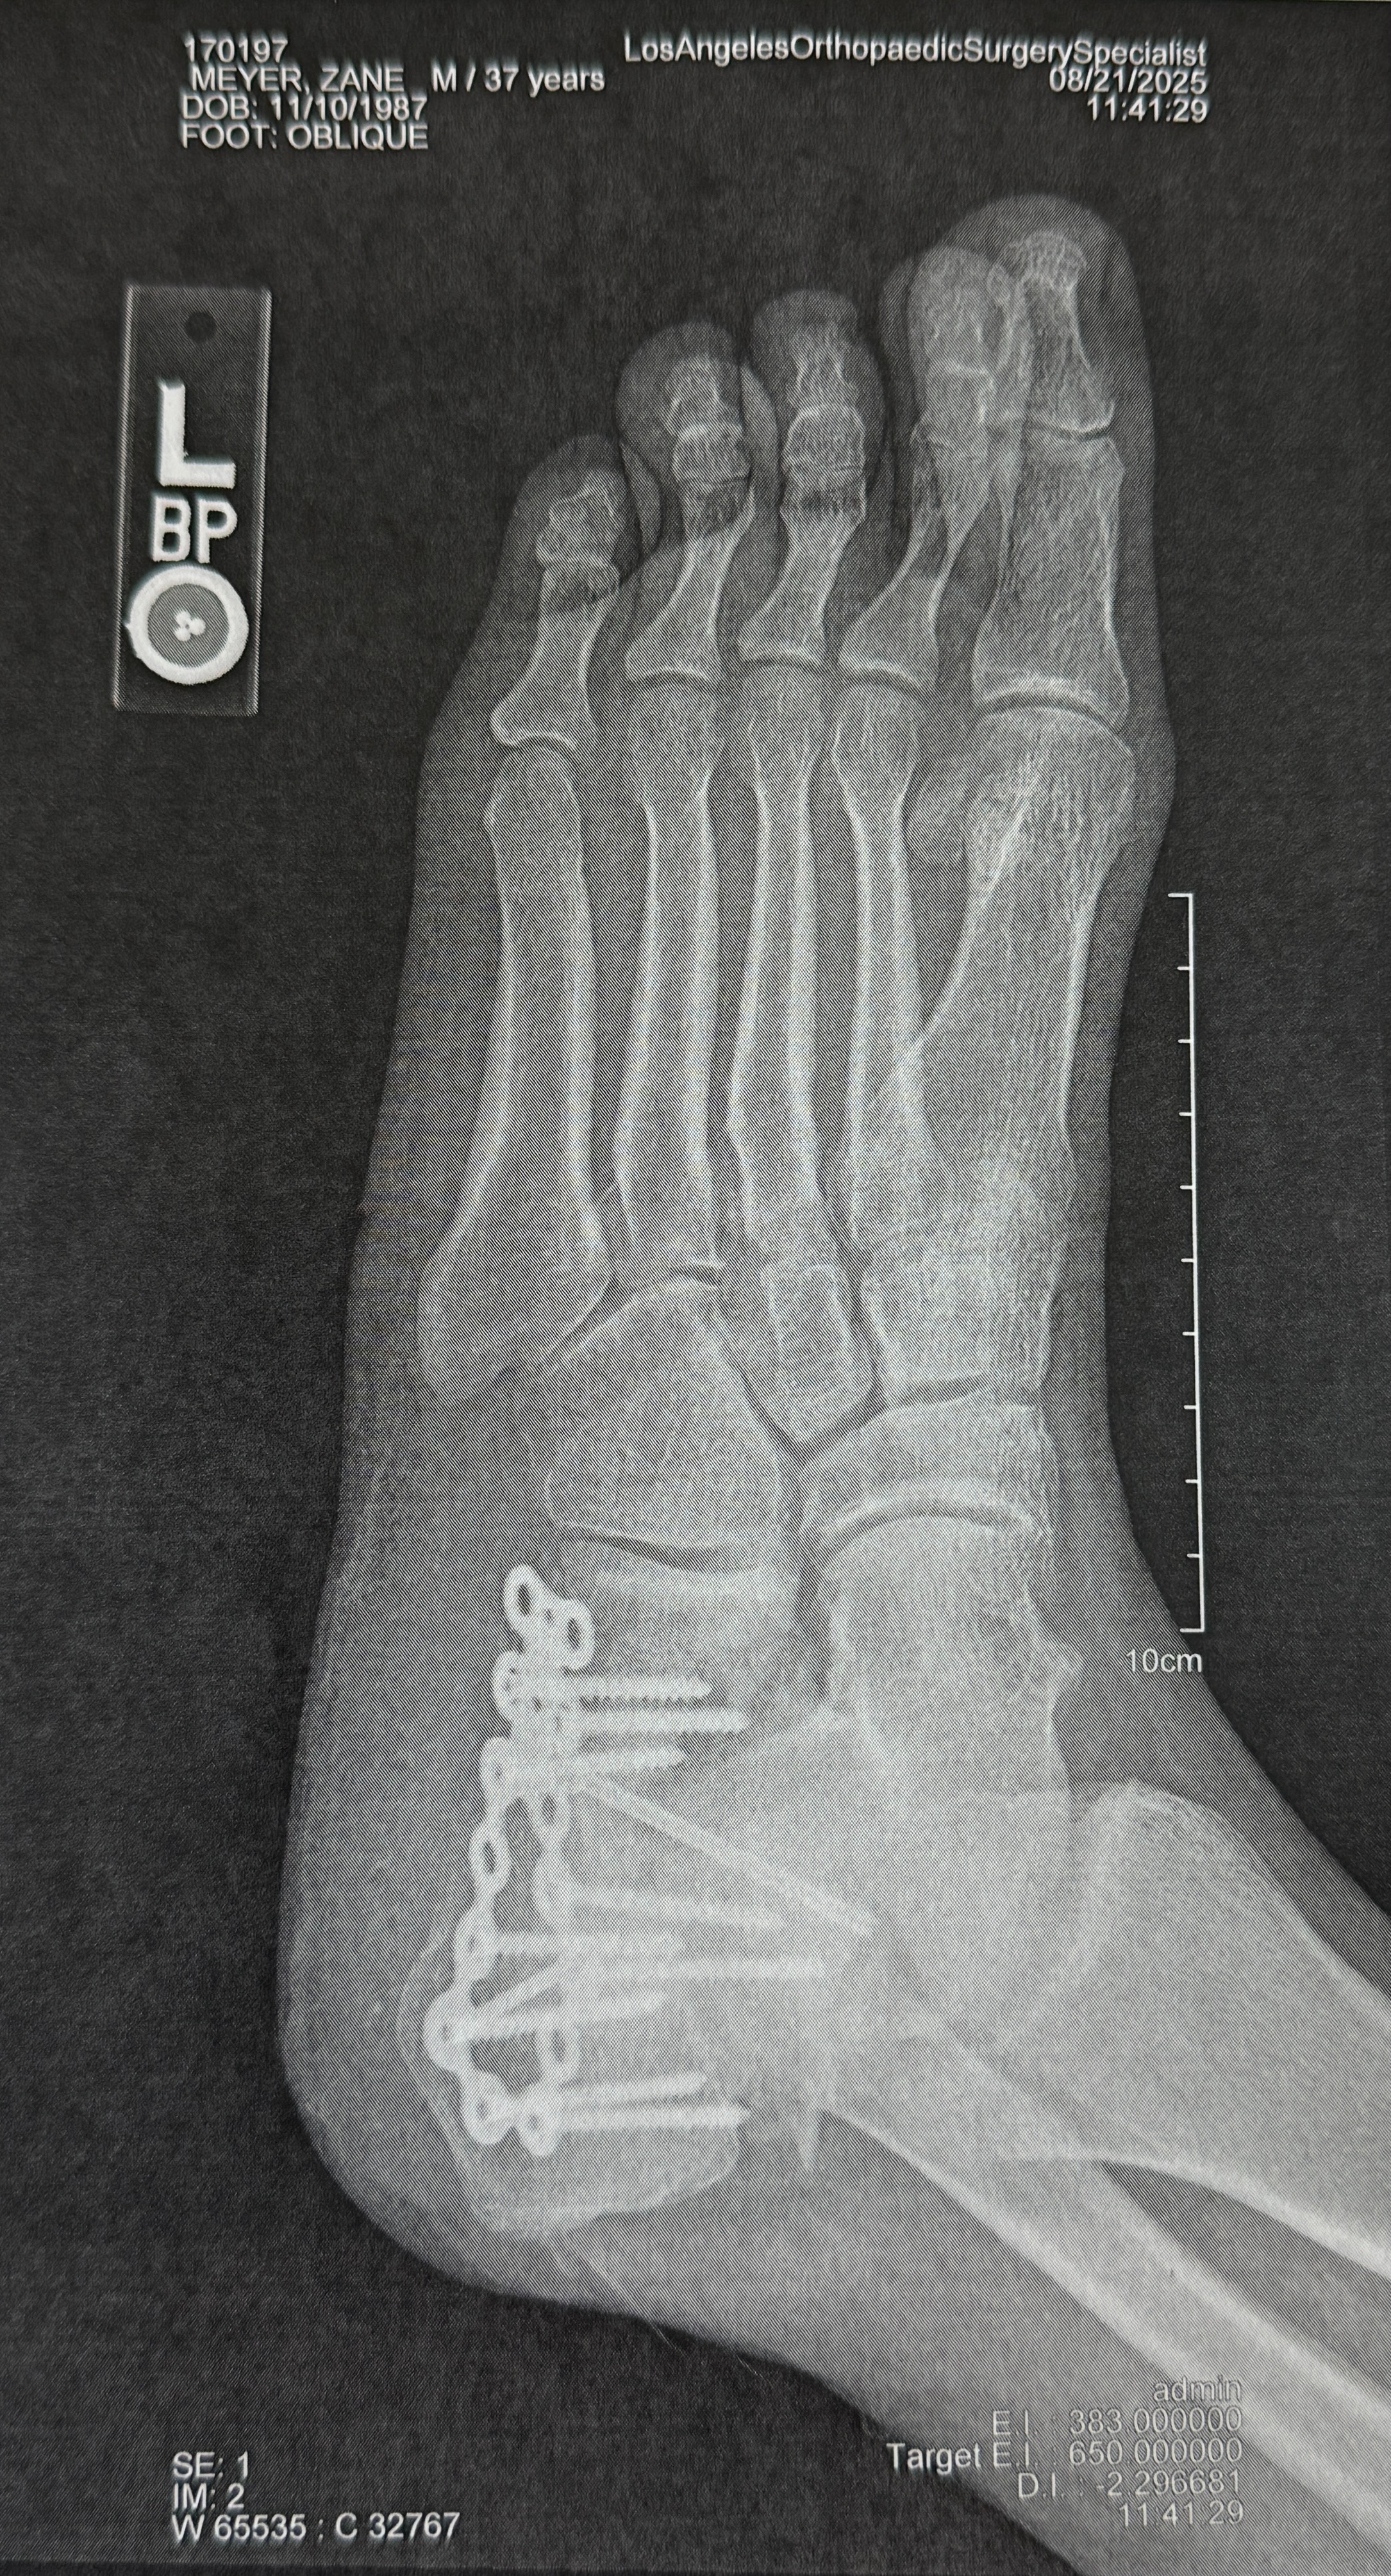

Last month, I suffered a devastating accident that shattered my heel and left me in debilitating pain and unable to work. The injury was so severe it required intensive surgery and I now face a long road to recovery. My doctor told me I’ll never walk the same again. I’ll be dealing with chronic pain and a bone fusion surgery is likely within the next 1–3 years. On top of that, my insurance had lapsed, so every medical bill has been out of pocket.